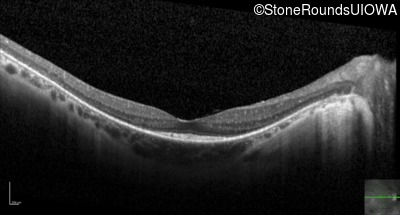

Optical Coherence Tomography - Left - 20/20 -2

Exemplar / OCT Stack